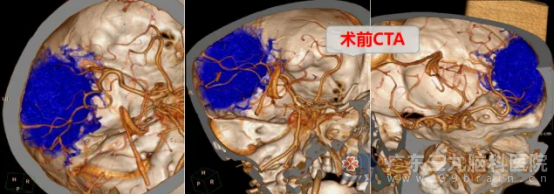

入院时,患者的言语仍偶有混乱。我院神经外十科专家为患者完善相关检查后,发现患者的左侧额颞顶部颅骨内板下占位侵犯邻近颅骨,范围约78mm×26mm×66mm,周围脑叶水肿且可疑受累,占位血供丰富,怀疑是不典型脑膜瘤可能性极大。

面对挑战,神经外十科团队迅速集结,深入研讨,审慎评估,制定周密手术方案。排除手术禁忌后,1月10日,一场与病魔的攻坚战打响。神经外十科学术带头人欧阳辉教授和副主任林德留带领医疗团队,凭借精湛技艺与丰富经验,如精细的工匠,在错综复杂的脑部组织间,小心分离肿瘤,全力守护正常组织,最终成功全切拳头大小的肿瘤。手术顺利完成。术后病理为脑膜皮细胞型脑膜瘤,CNS WHO1级,属于良性肿瘤。